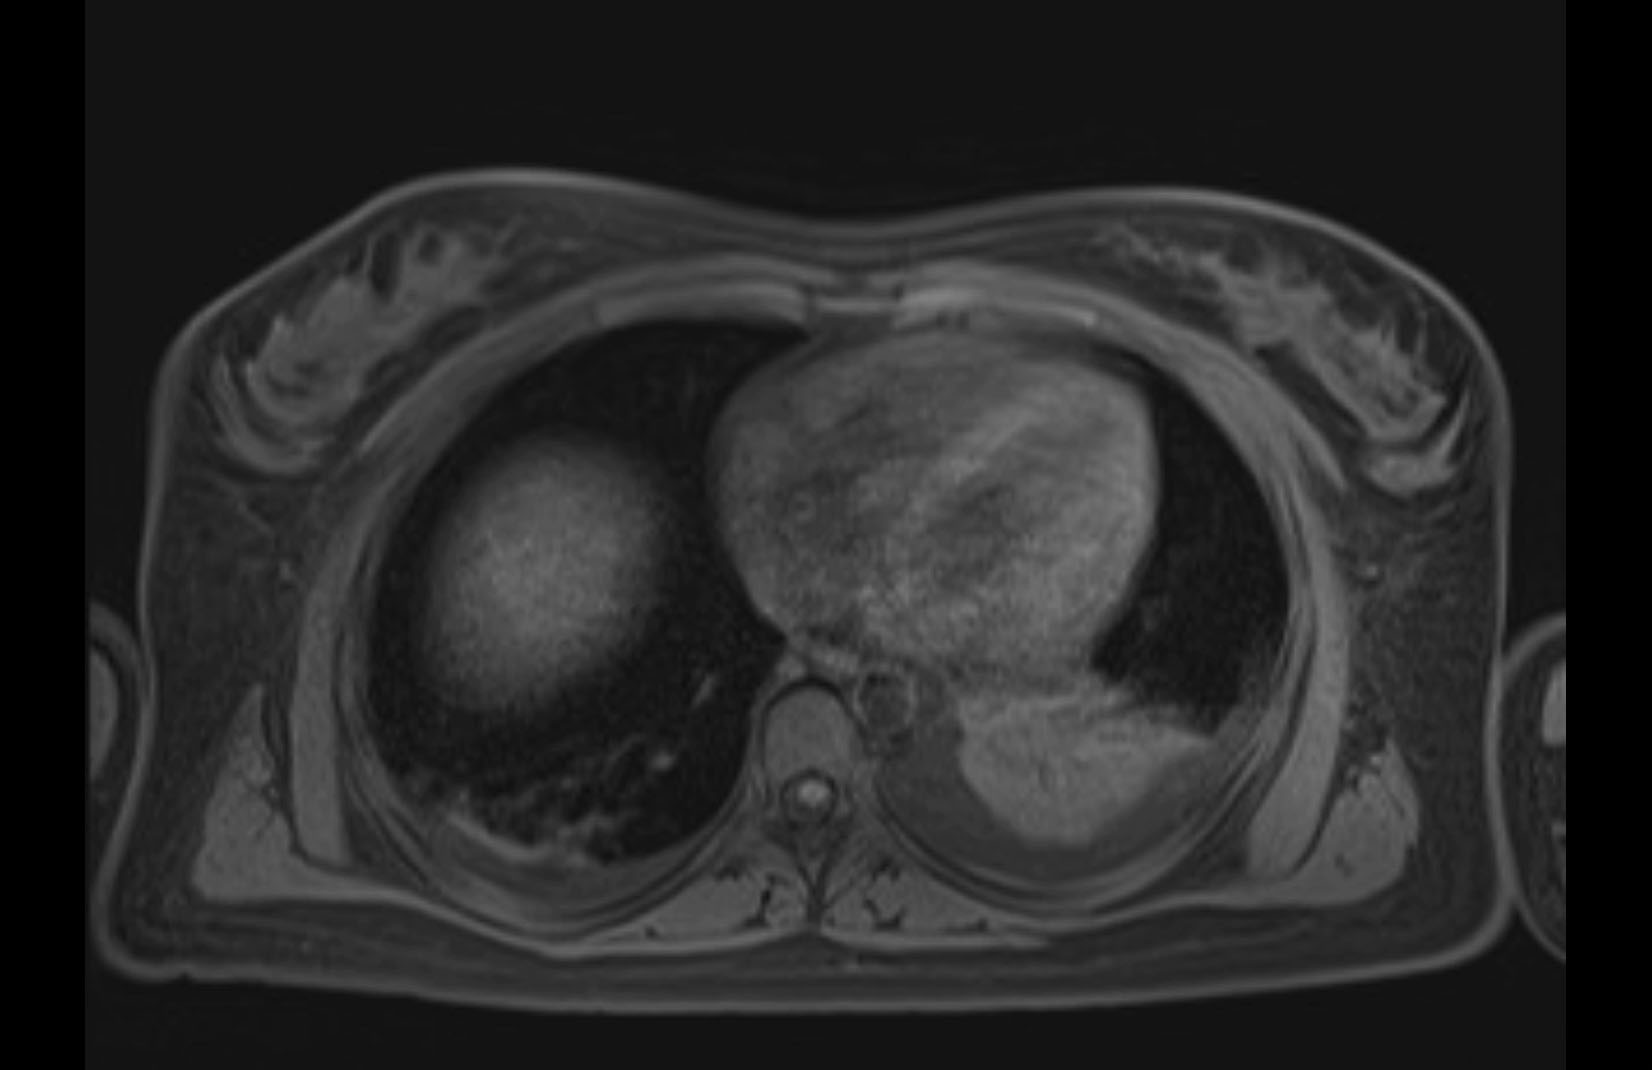

MRI T1

MRI T2